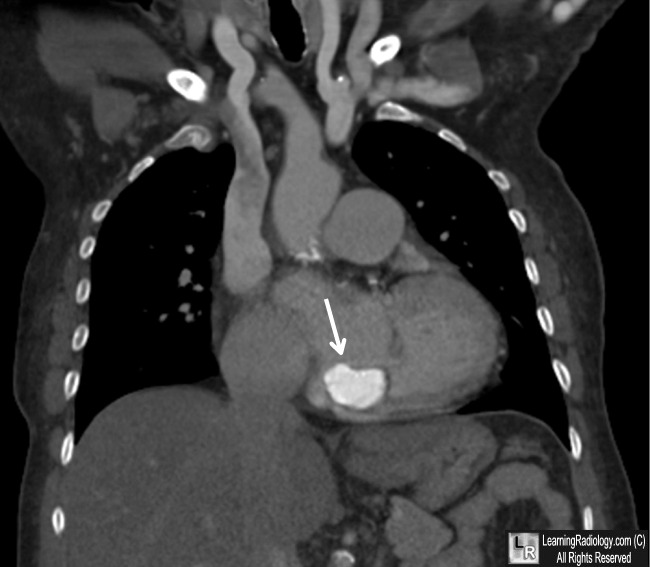

Large Caseous Mitral Medicine Annular Calcification

Texas Heart Institute Journal Caseous Calcification of the Mitral Annulus 911 that might have developed between the tip of the ante-rior mitral valve leaflet and the sigmoid septum during ... Read Full Source